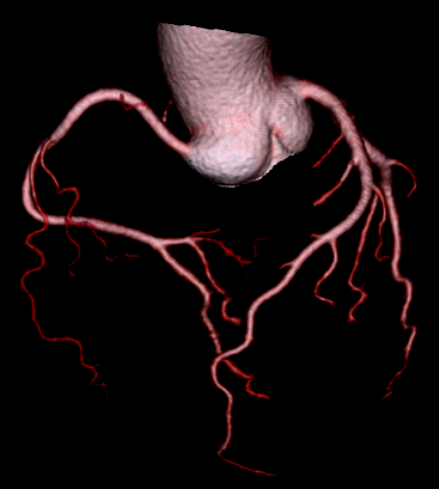

极速响应,守护生命

配备业界领先的320排超宽探测器,单圈扫描仅需0.28秒,可快速完成三维动态影像采集。适用于急诊CTA、脏器灌注评估及冠状动脉、头颈动脉等复杂部位成像,为脑出血、胸痛三联征、主动脉夹层等危急重症争取“黄金时间”,助力神经、胸腹、肌骨等急诊场景高效处置。